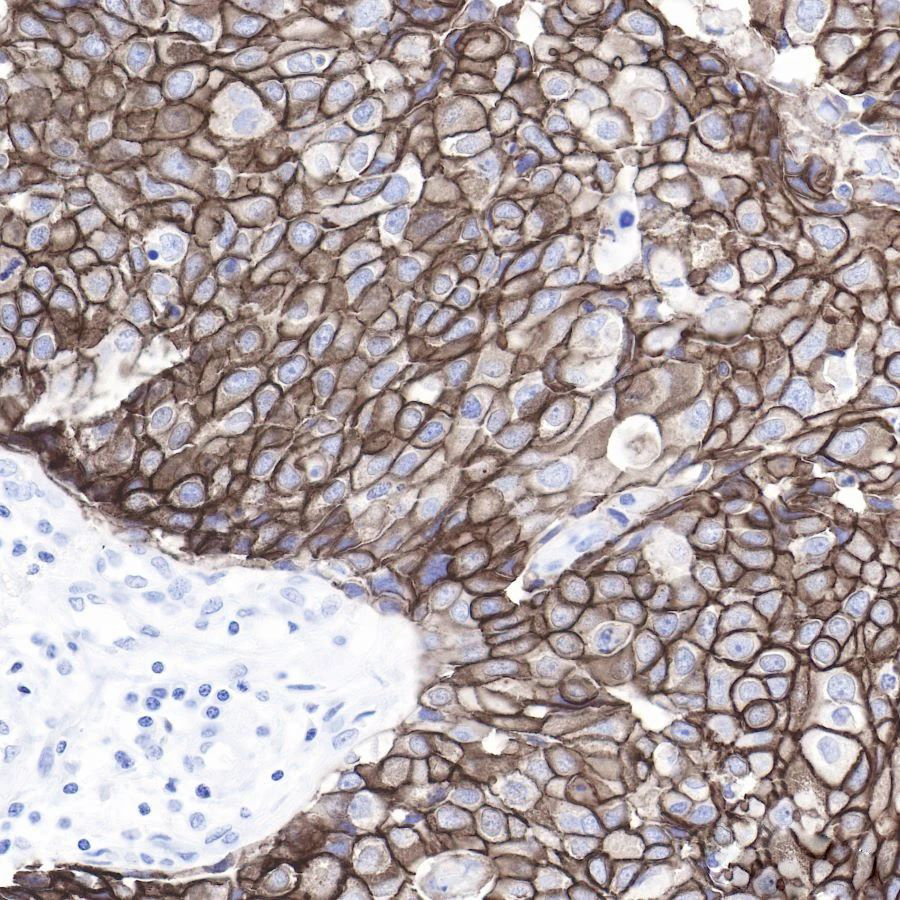

免疫组织化学(IHC)技术是一种通过标记特异性抗体来检测抗原的细胞化学方法。在乳腺癌检测中,IHC技术被广泛应用于HER2、ER、PR等乳腺癌相关抗原的检测。其中,HER2蛋白过表达的检测对于指导靶向治疗具有重要意义。斯达特的乳腺癌相关抗体,正是基于IHC技术而研发,为精准诊断和治疗乳腺癌提供了可靠的工具。

1、ErbB2

HER2 (ErbB2) 是人类表皮生长因子受体(HER/EGFR/ERBB)家族的一个成员。但与ERBB家族的其他成员相反,HER2并不直接结合配体。例如在癌症中,HER2的激活来自于与另一个ERBB成员的异源二聚体或当HER2浓度高时的同源二聚体。HER2基因的扩增或过度表达,从而促进肿瘤的生长和进展。HER2阳性乳腺癌患者通常具有更高的肿瘤增殖活性、更强的侵袭能力和更短的生存期。近年来,该蛋白已成为约30%的乳腺癌患者的重要生物标志物和治疗靶点。